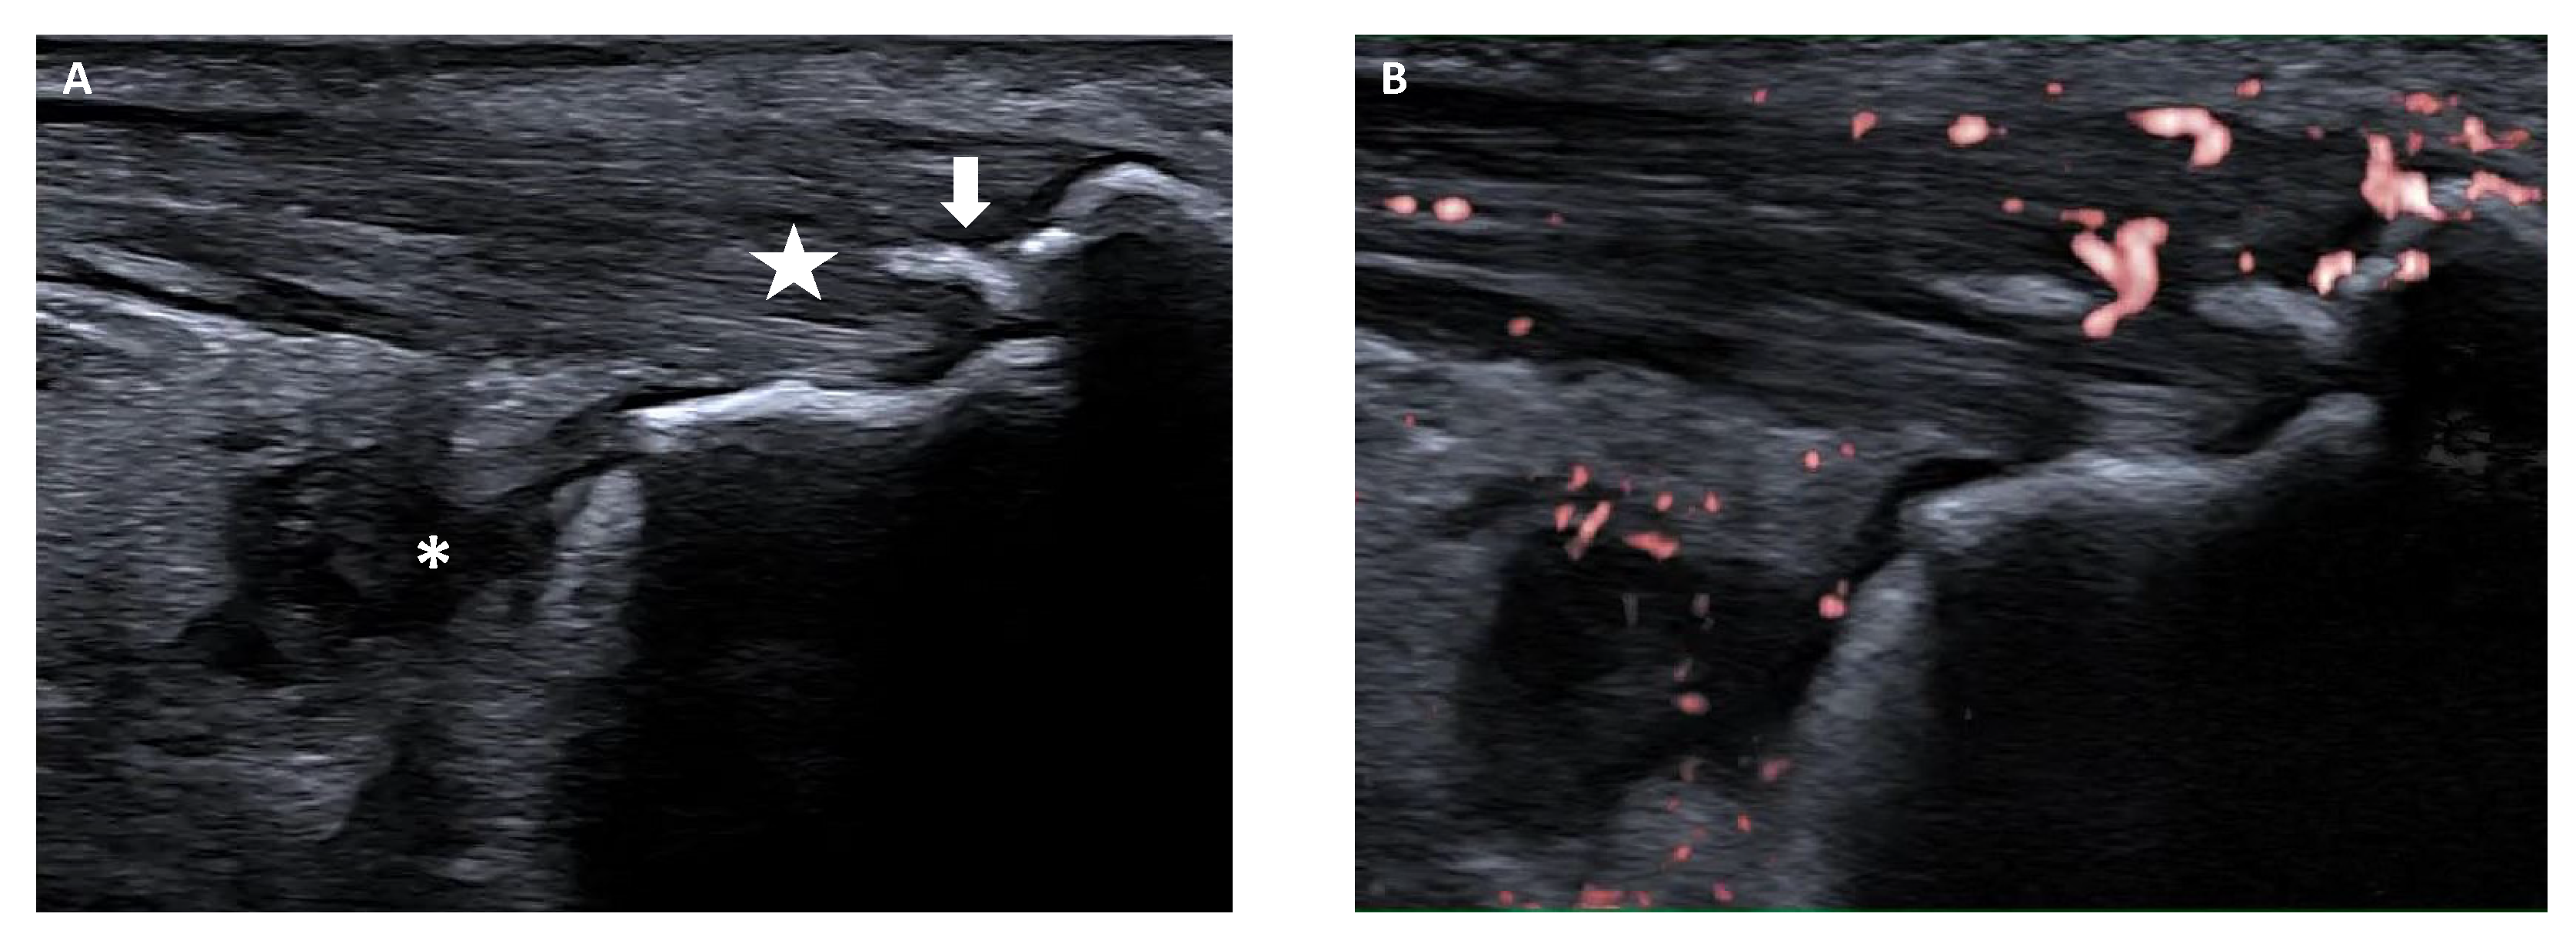

- Balint, P.V.; Terslev, L.; Aegerter, P.; Bruyn, G.A.W.; Chary-Valckenaere, I.; Gandjbakhch, F.; Iagnocco, A.; Jousse-Joulin, S.; Möller, I.; Naredo, E.; et al. Reliability of a consensus-based ultrasound definition and scoring for enthesitis in spondyloarthritis and psoriatic arthritis: An OMERACT US initiative. Ann. Rheum. Dis. 2018, 77, 1730–1735. [Google Scholar] [CrossRef]

- Rossi-Semerano, L.; Ravagnani, V.; Collado, P.; Vojinovic, J.; Roth, J.; Magni-Manzoni, S.; Naredo, E.; D’Agostino, M.A.; Jousse-Joulin, S. Validity of ultrasonography in detecting enthesitis in children: A systematic literature review. Jt. Bone Spine 2023, 90, 105538. [Google Scholar] [CrossRef]